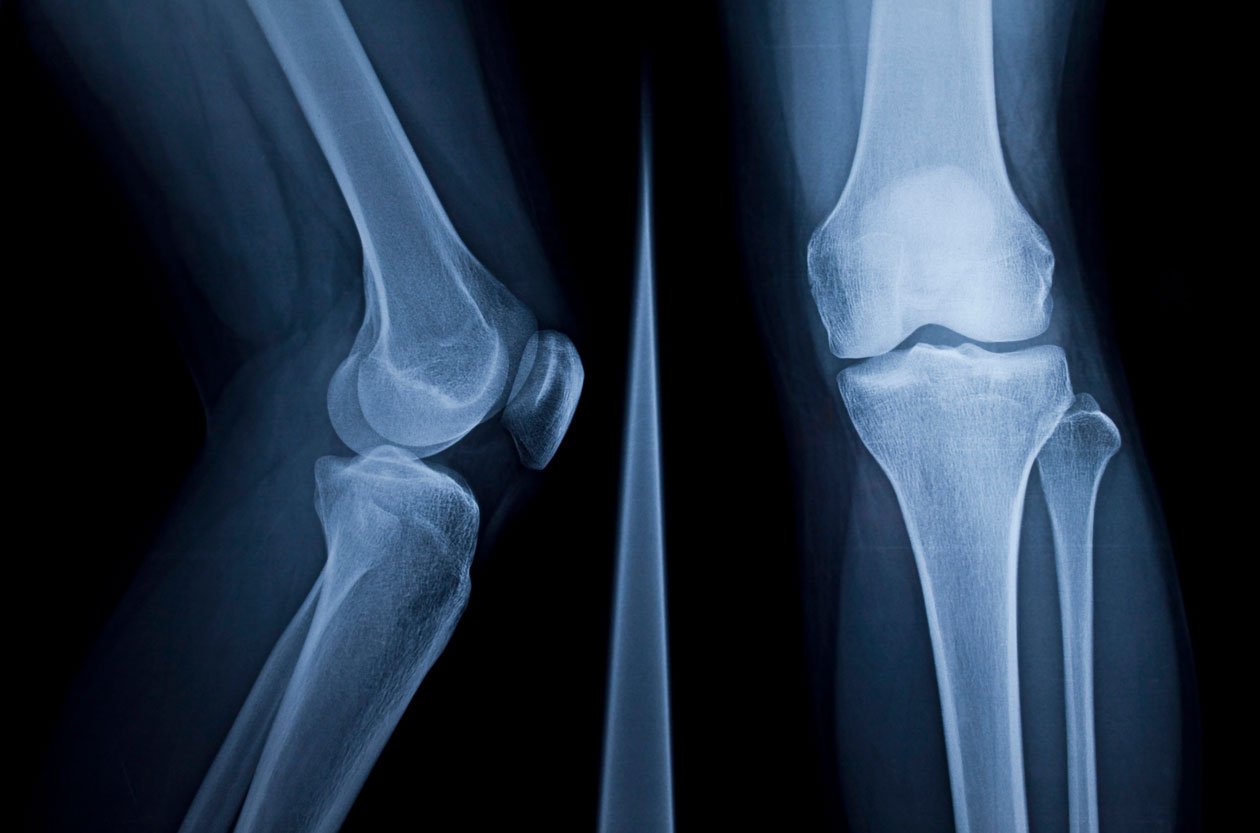

Η άρθρωση του γόνατος αποτελείται από τρία οστά, το μηριαίο οστό (μηριαίο οστό), την επιγονατίδα (επιγονατίδα) και την κνήμη (κνήμη). Σε σχέση με αυτά τα οστά, διαμορφώνονται τρία διαμερίσματα του γόνατος:

• Το έσω (εσωτερικό) διαμέρισμα του γόνατος.

• Το έξω (εξωτερικό) ή πλάγιο διαμέρισμα(στο σημείο που αρθρώνεται το κατώτερο τμήμα του μηριαίου οστού με το ανώτερο τμήμα της κνήμης)

• Το επιγονατιδομηριαίο διαμέρισμα, στο σημείο άρθρωσης της επιγονατίδας με το μηριαίο οστό.

Η αρθρίτιδα του γόνατος μπορεί να εμφανιστεί σε οποιοδήποτε από αυτά τα διαμερίσματα, ωστόσο εκδηλώνεται πιο συχνά στο έσω διαμέρισμα και λιγότερο στο έξω διαμέρισμα. Η αρθρίτιδα που περιορίζεται στο επιγονατιδομηριαίο διαμέρισμα του γόνατος είναι πιο σπάνια.

Η μονοδιαμερισματική αρθροπλαστική του γόνατος αφορά στην αντικατάσταση του επιμέρους διαμερίσματος της άρθρωσης (έσω, έξω ή επιγονατιδομηριαίο), στο οποίο εντοπίζεται η βλάβη. Το κατεστραμμένο τμήμα αφαιρείται χειρουργικά και αντικαθίσταται με πρόθεση (τεχνητό γόνατο). Σε αντίθεση με την ολική αρθροπλαστική του γόνατος, κατά την οποία αντικαθίσταται, ολόκληρη οι άρθρωση, κατά την μονοδιαμερισματική αρθροπλαστική δεν κόβονται οι σύνδεσμοι. Ως εκ τούτου, με τη μονοδιαμερισματική αρθροπλαστική επιτυγχάνεται η βέλτιστη δυνατή λειτουργικότητα του γόνατος μετεγχειρητικά.